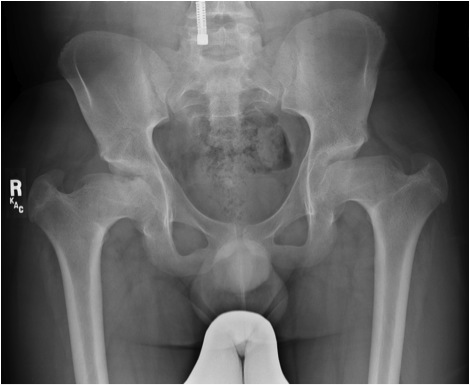

Hip

Most frequently & severely involved

- Coxa vara

- small irregular & fragmented capital epiphyses

- progressive flattening & extrusion of head

- poor head coverage

Premature OA common

Management

- valgus intertrochanteric osteotomy +/- shelf